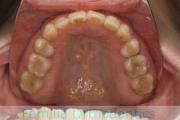

- ≫治療前

上顎

下顎

前歯の関係など

- ≫治療中 ステップ1

- ≫治療後